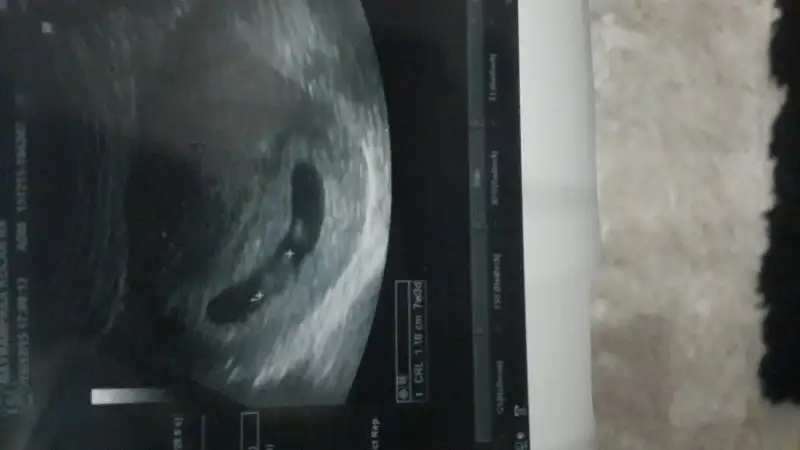

Bir de bu var canım..plasentayı göremedim canım. Kusura bakma. Bu kızının ki mi?

Plasenta kesenin altını tamamen kaplamış gibi gördüm ben canımBir de bu var canım..

Yani sağda veya solda değil mi canim ..Plasenta kesenin altını tamamen kaplamış gibi gördüm ben canım

Ayırtedemedim canım.Yani sağda veya solda değil mi canim ..